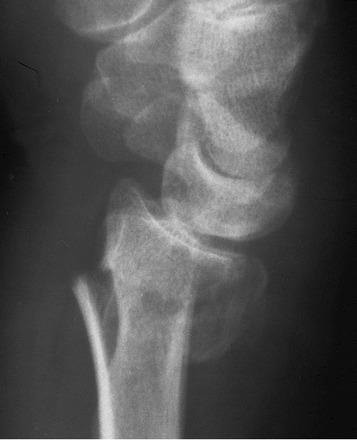

Eponymous fractures and fracture-dislocations are most commonly named after the doctor who first described them.